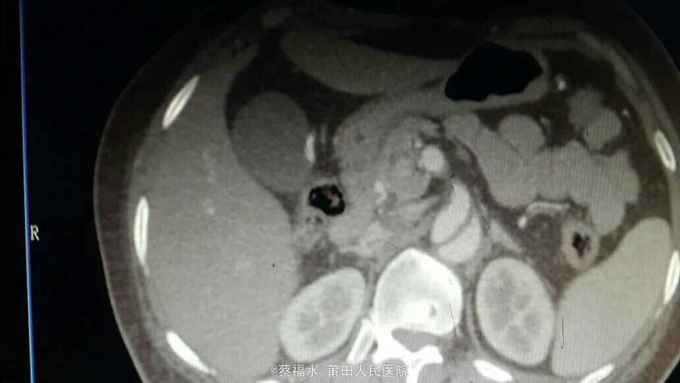

女性患者,56岁,以“上腹部、左腰部突发疼痛2小时”为主诉入院。入院查体:HR70次/分,BP220/105mmHg,双肺呼吸音清,未闻及干湿性啰音,心律齐,各瓣膜区未闻及杂音,腹平软上腹部压痛明显,无反跳痛,胆囊区无压痛,墨菲氏征阴性,肝脾肋下未及,左肾区叩痛可疑阳性,肠鸣音约5次/分。入院后查血淀粉酶正常,肌钙蛋白I阴性,心肌酶谱正常,心电图无心肌缺血改变,上腹部+胸部CT提示:右肾囊肿,余未见明显异常。予抑酸、维生素K3、曲马多等应用后,患者仍腹痛剧烈,性质同前,无明显缓解。予完善胸主动脉、腹主动脉、髂动脉CTA结果如下:

腹主动脉夹层动脉瘤 予控制血压、控制心率等治疗,患者腹痛较前缓解